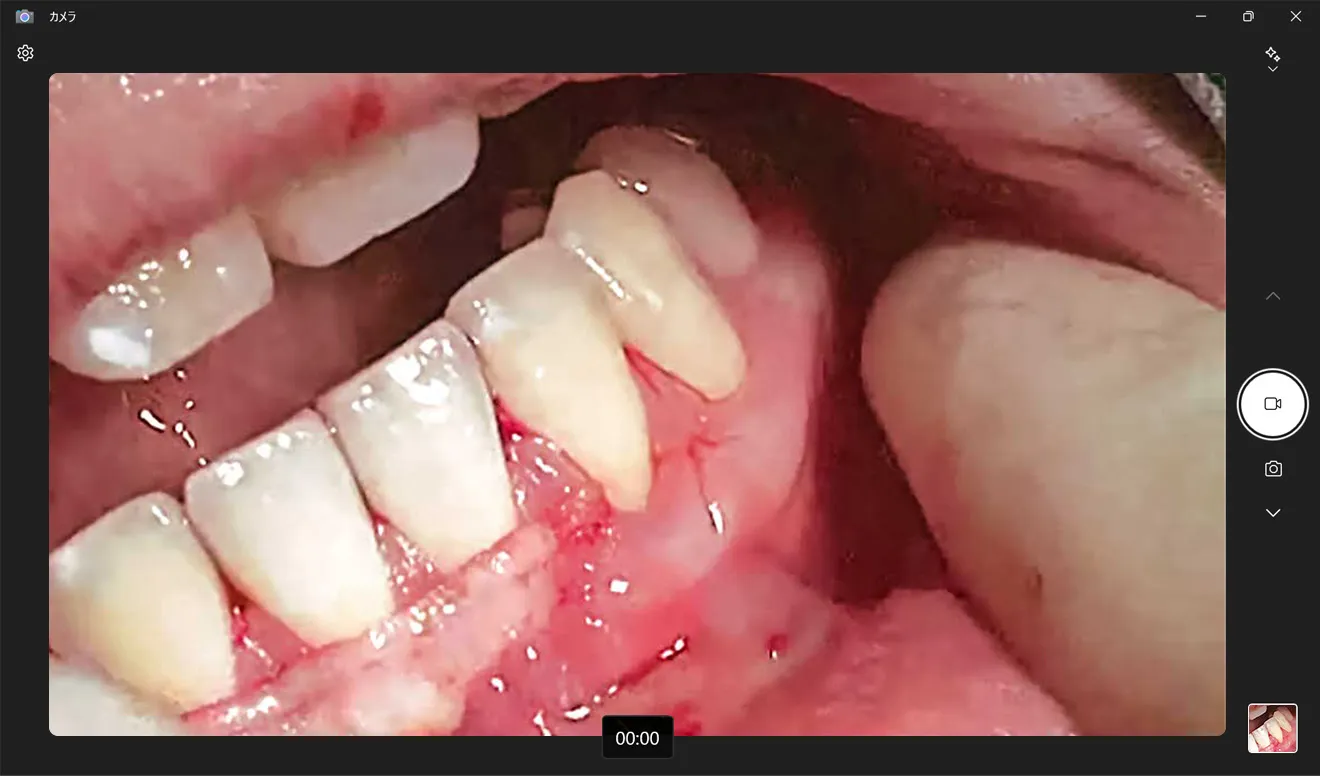

“サージカム HD”は、サージテルに搭載できる専用の小型カメラシステム。実際に診療をしている術者と“同じ視点”を克明に録画し、さまざまなシチュエーションでの活用が期待できます。

撮影が難しい口腔内の施術部位も、術者視点でしっかり捉えて撮影できます。

たとえば粘液貯留嚢胞の切除では、切開線の位置や方向、嚢胞を剥離する際のハサミの操作など、細かな部分まで客観的に把握できます。

なかでも「勉強になった」と言われるのは、切開の方法、剥離の加減、形成の仕方――。支台歯形成は患者さまの開口量、頬や舌の位置、歯列の状態、歯の位置により難易度が変わってきます。いろいろなパターンを見ることで、技術の安定化にもつながっていると思います。